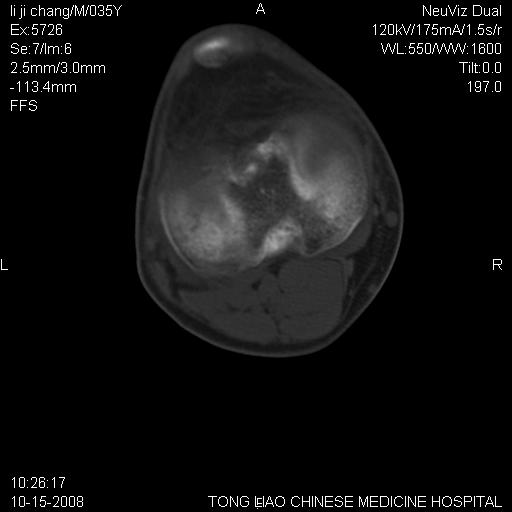

男,35岁,骨科诊断骨性关节炎。继往使用过激素,现股骨头坏死。膝关节病变,请会诊

一元论-----亦考虑为坏死

支持考虑无菌坏死

支持无菌坏死伴退行性骨关节病.

剥脱性骨软骨炎:是一种关节下软骨及软骨下骨缺血性坏死。

支持 无菌性坏死伴退行性骨关节病。

支持无菌坏死伴退行性骨关节病